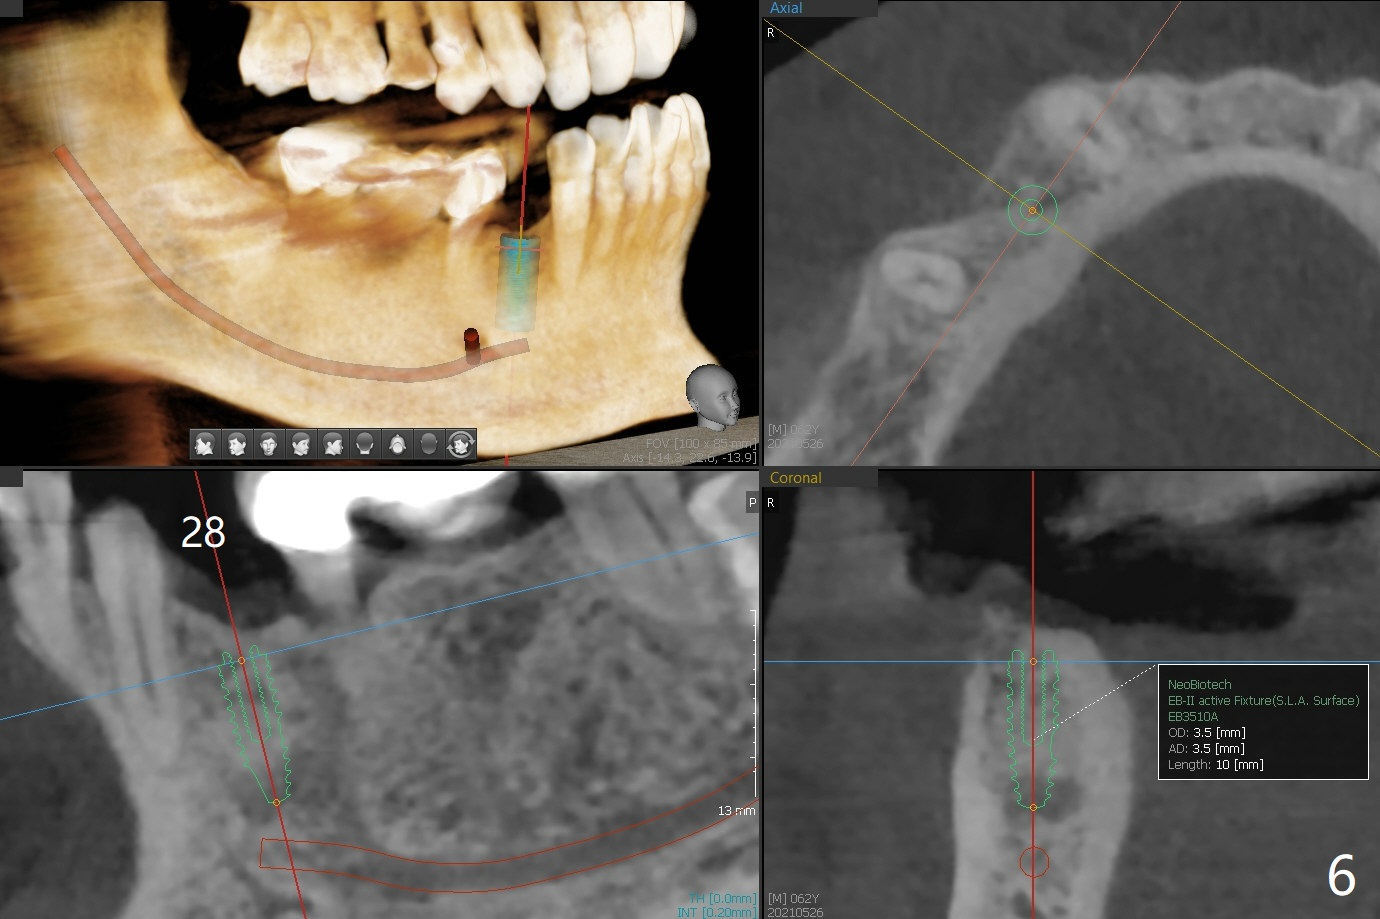

A 62-year-old man with sign of bruxism (#19 porcelain chip (Fig.2), 28 fracture/extraction) complains of severe mastication pain at #15 (Fig.1). More severe pain is elicited when the buccal cusps bite on a bite stick than the palatal one (Fig.3 with suspicious crazing lines). CT shows bone loss around the palatal root (Fig.4 P). A 5x11.5 mm implant will be placed immediately (Fig.5). The bone at #28 is able to hold a 3.5x13 mm implant (Fig.6). It is extremely difficult to take photos for 2nd molar crack line with a regular camera (Fig.3). The Shining Oral Scanner acts additionally as an intraoral camera. As a busy clinician, I do not have time to take photos for #19 porcelain chip. My assistants take over the task. After work, I am able to have bumper harvest. With the information just mentioned, I will be in a better position to present a more comprehensive treatment plan to the patient when treatment at #15 is finished: remove #18-20 bridge, place an implant at #19 and fabricate new crowns at #18 and 20.